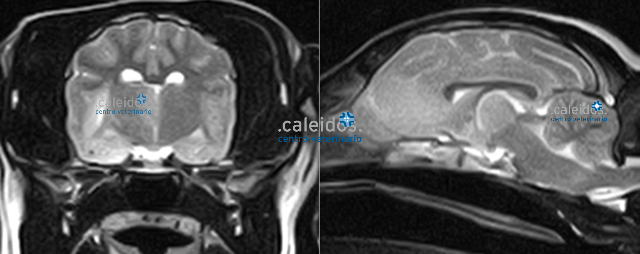

Getting to the bottom of the root of your pet's illness is our goal at Caleidos clinic, so it's essential to use every tool that can allow us to achieve it. Among these are MRI. This investigation, due to its scarce availability in the area and in particular in the veterinary field, although particularly suitable for the study of soft tissue and minimally invasive (it requires only mild sedation and does not emit harmful radiation for the animal), was, for years, performed only after resorting to other more widespread and easier techniques. Today, MRI is known as the diagnostic method of choice for brain, medullary, ligament, cartilage and some cardiovascular diseases, ones that can be promptly identified in our facility thanks to a cutting-edge, highly performing MRI equipment and to specialist staff.